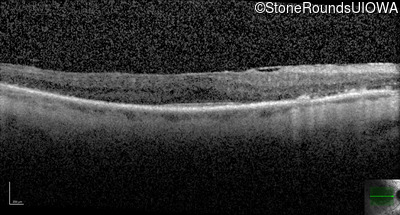

Optical Coherence Tomography - Right - 20/40 -1 sc

Exemplar / OCT Stack